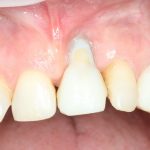

Рекомендации по установке имплантов. Для всех. Часть V.